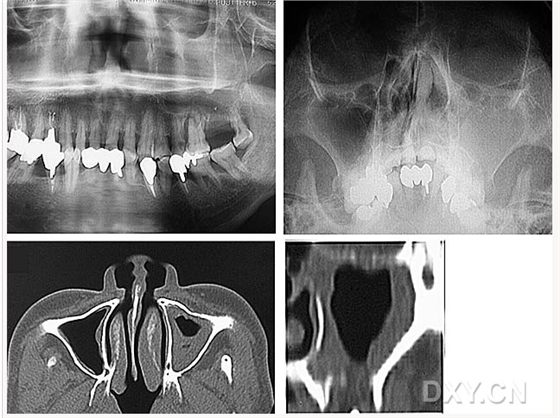

鼻鄂囊腫

鼻腭囊腫